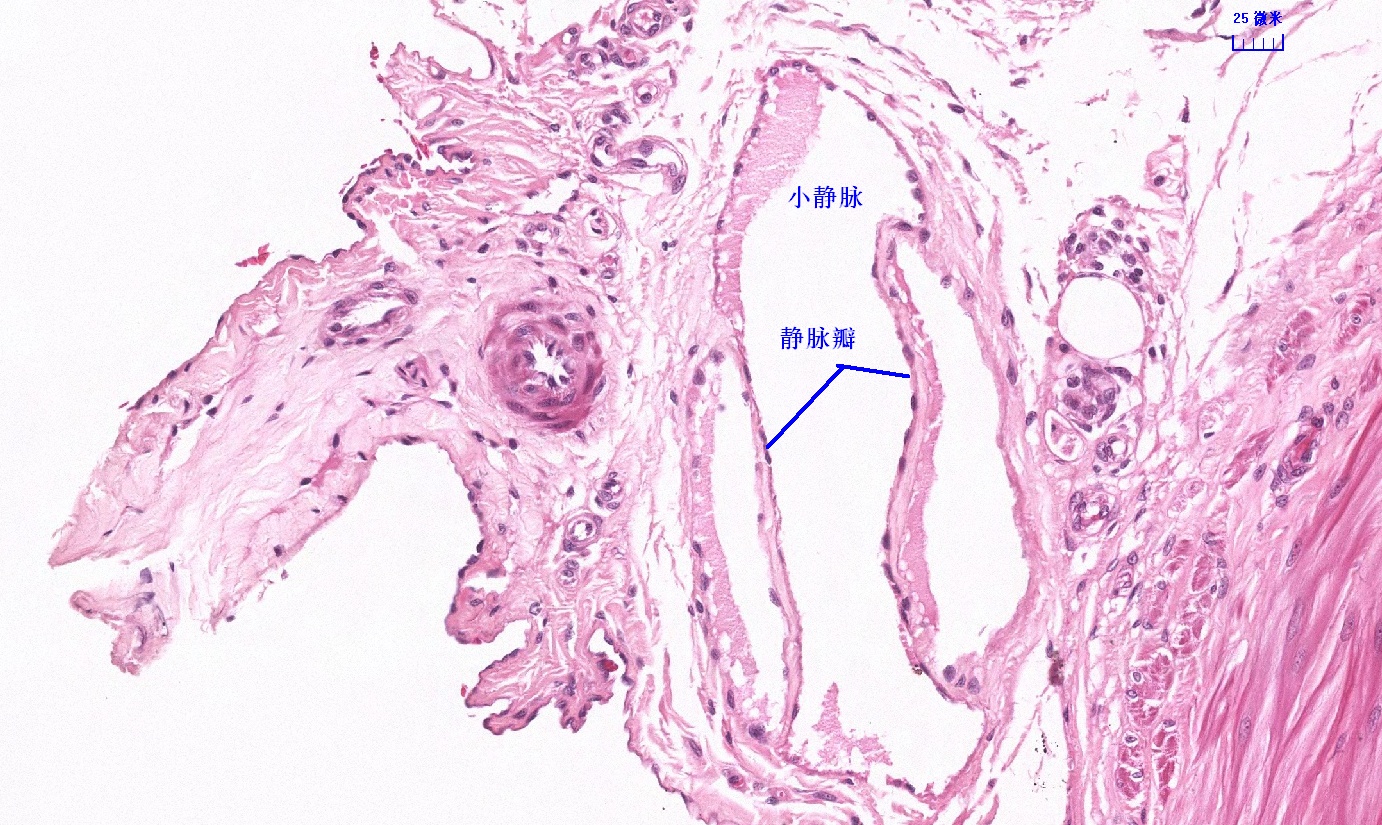

6.1 循环系统切片库